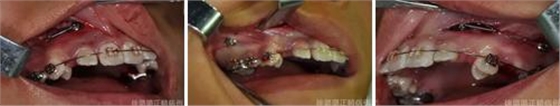

導(dǎo)萌術(shù)中口內(nèi)像